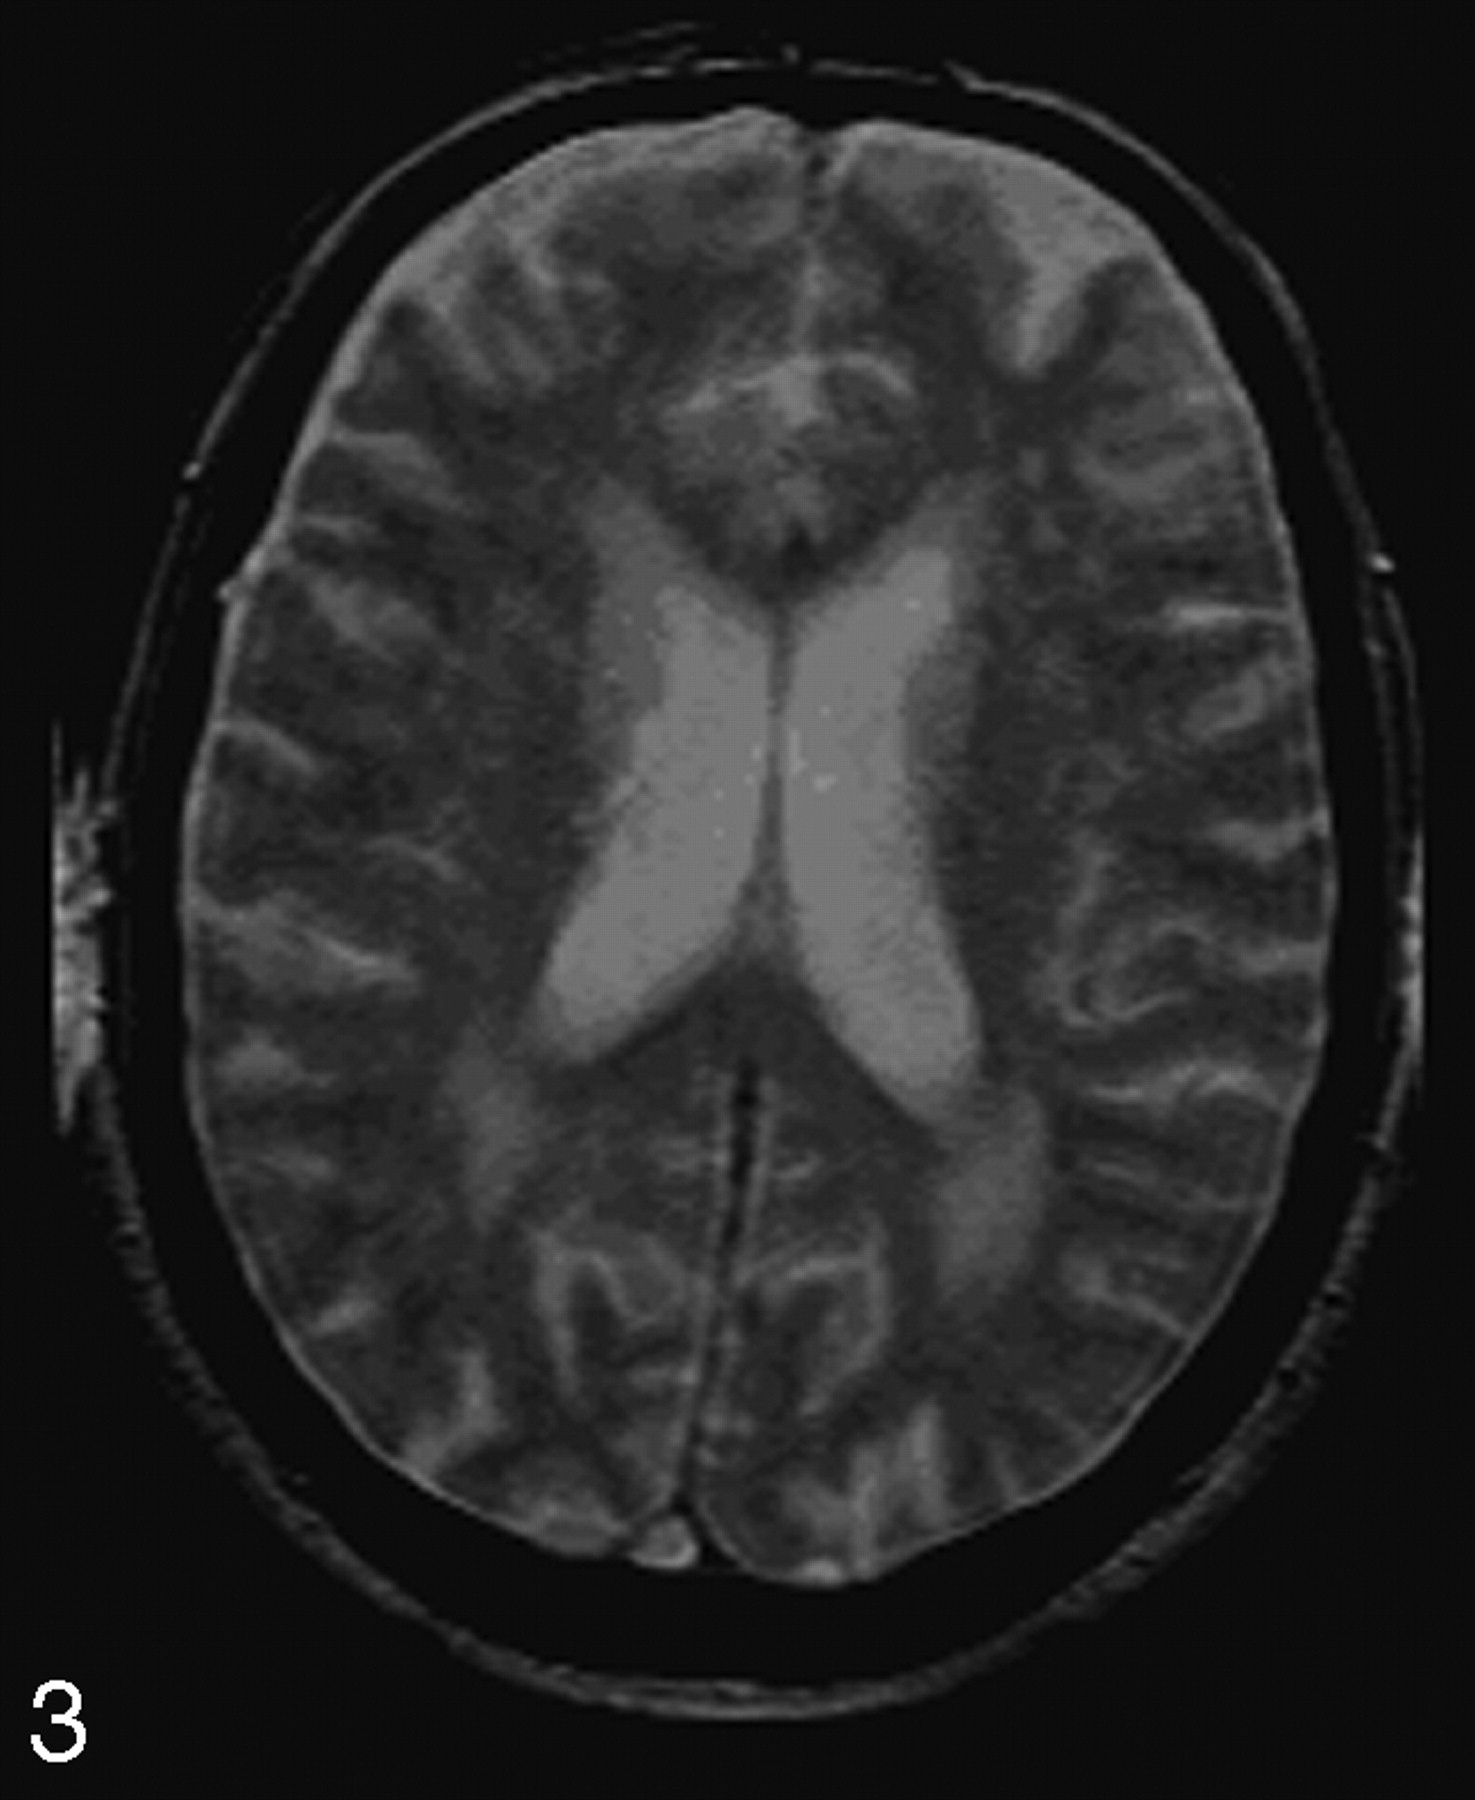

After categorizing, one rater identified on MTI, acquired with the saturation pulse (having a PD contrast), the lesions that were detected on the T2-weighted, PD, and FLAIR images (Fig 3). The rater subsequently outlined manually the PVWMH and DWMH on these MTIs, in the study group, by using 3DVIEWNIX image processing software (Department of Radiology, Hospital of the University of Pennsylvania, Philadelphia, Pa). In the study and control group, normal-appearing periventricular white matter and deep white matter were manually outlined. Deep normal-appearing white matter was outlined in the semioval center by placing four 5 ×5 pixels in large regions of interest. The same regions of interest were used for sampling periventricular normal-appearing white matter. No samples were taken from periventricular normal-appearing white matter if periventricular lesions were present. For all outlined regions, volume and mean MTR were calculated. MTR was defined as the percentage of change in signal intensity between the scans with and without the saturation pulse, as shown in the following equation11:

Example of an image from the MTI protocol, obtained with saturation pulse (Ms) and having a proton-attenuation weighted contrast. It clearly shows occipital periventricular white matter hyperintensities as well as deep white matter hyperintensities.